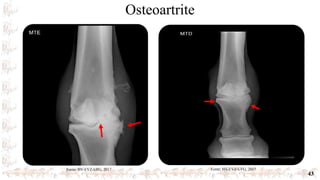

Osteoartrite

43

Fonte: HV-EVZ-UFG, 2017 Fonte: HV-EVZ-UFG, 2017